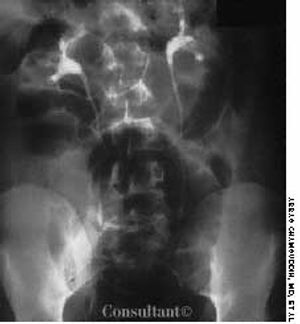

For the past 2 hours, a 19-year-old man had lower abdominal pain accompanied by nausea and vomiting. He had no fever and no diarrhea. Direct tenderness was mainly in the right lower quadrant, radiating slightly to the left lower quadrant. There was no significant rebound tenderness. The patient refused rectal examination.